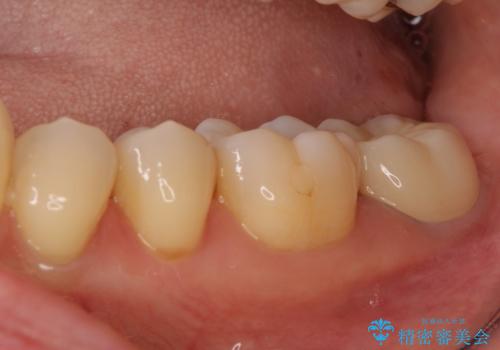

奥歯が割れた 神経が取り除かれた歯のセラミッククラウン治療

破折部位を除去したところ、外科処置が必要な深さまで破折線が及んでいなかったため、速やかにジルコニアクラウンにて補綴を行うことになりました。

神経が取り除かれた歯、特に奥歯では、歯の破折が起こりやすいので、クラウンによる補綴治療が必要であることを実感した治療でした。